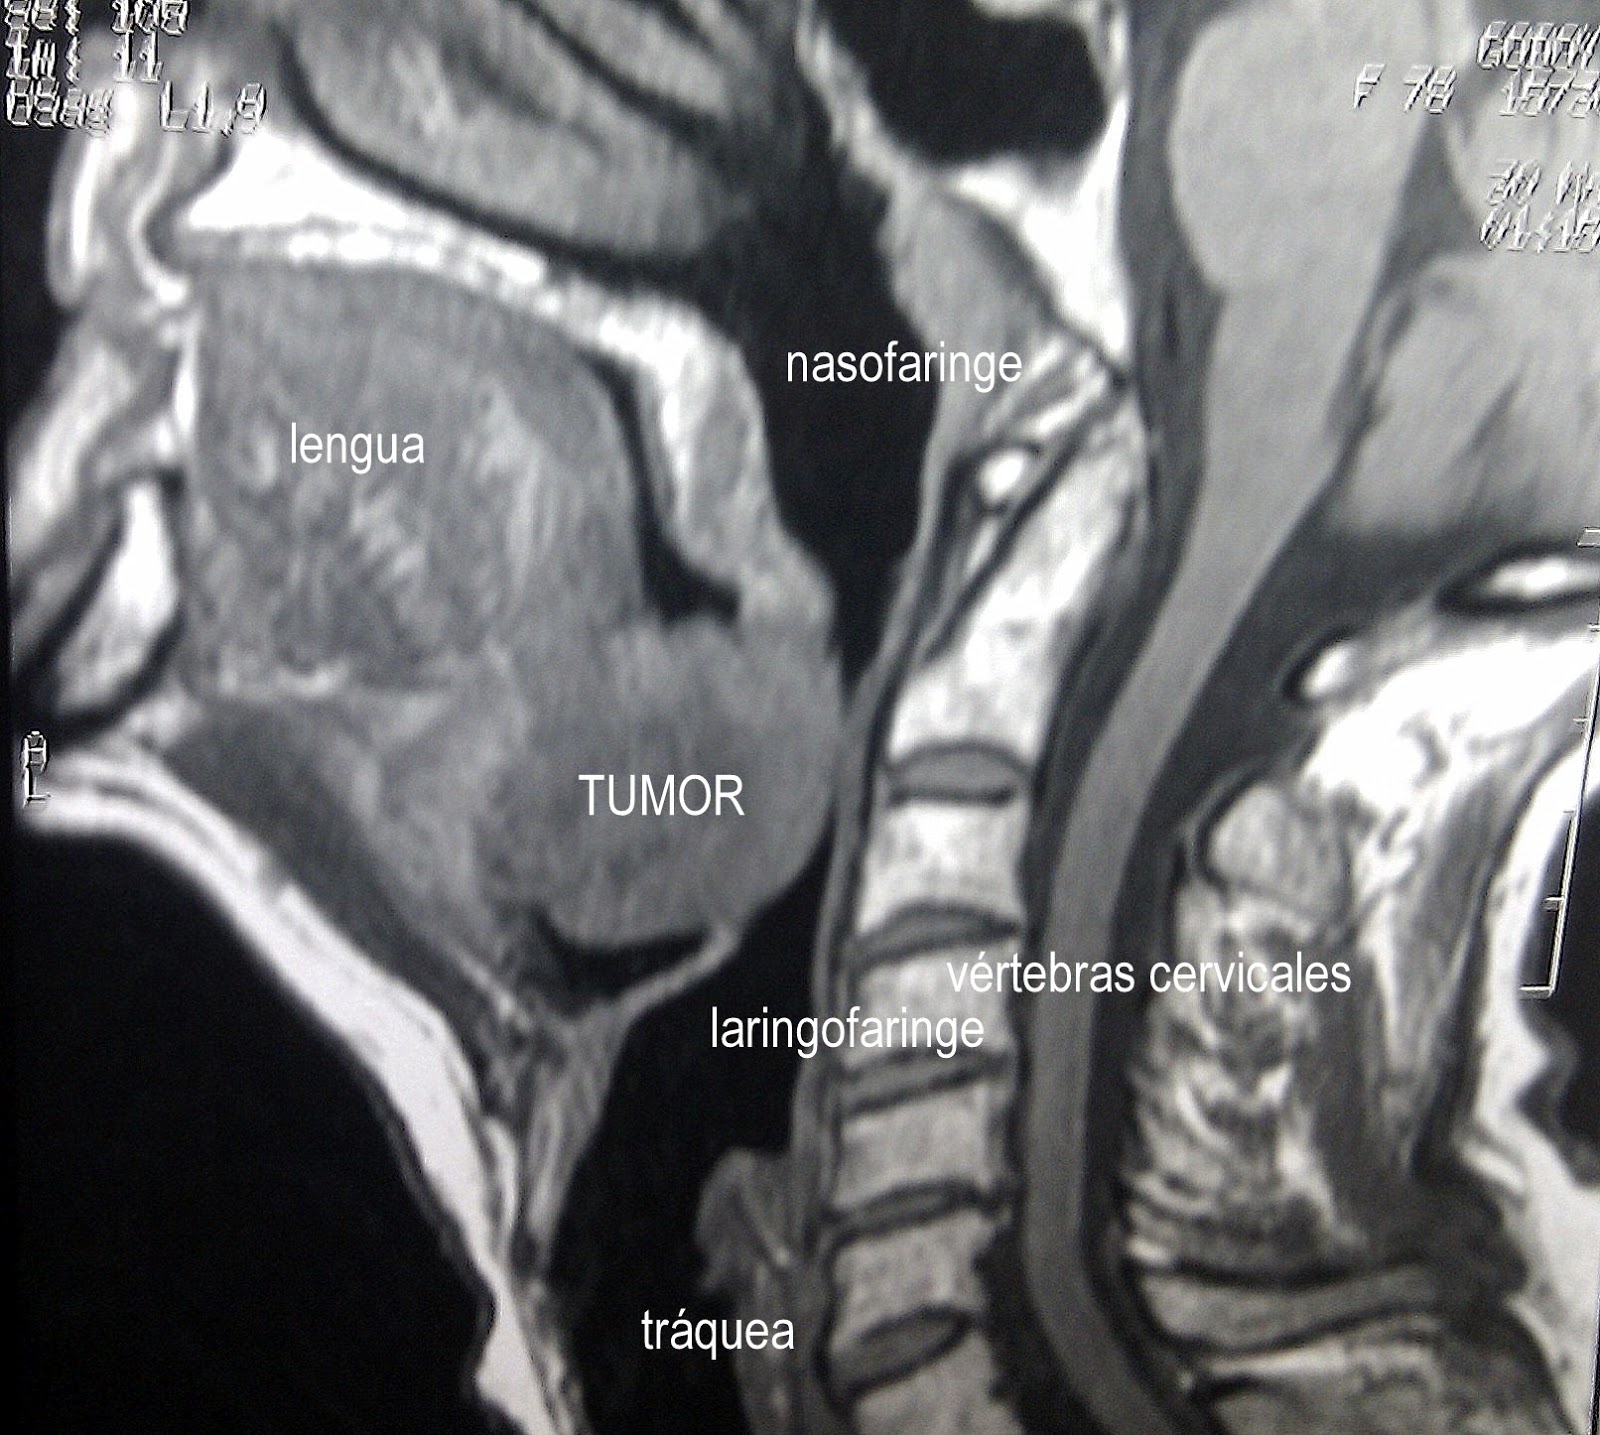

Tumores benignos de cabeza y cuello 😈